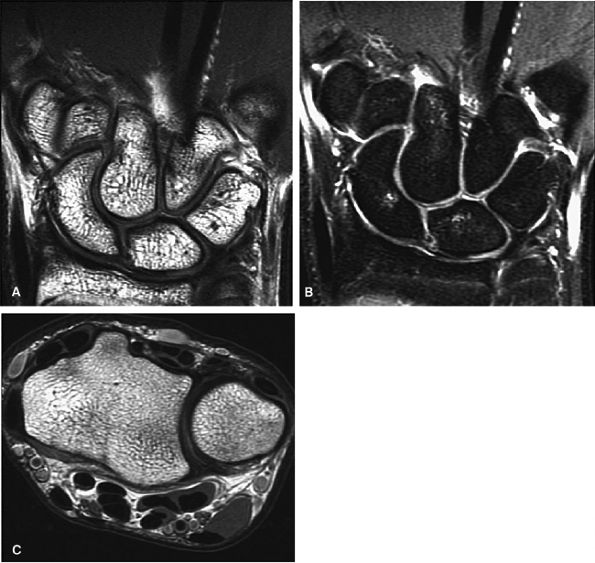

FIGURE 10.2 ● Optimized signal-to-noise in routine wrist imaging using a four-channel phased-array wrist coil on a 3T imager. (A) Coronal PD FSE image. (B) Coronal FS PD FSE image. (C) Axial PD FSE image.